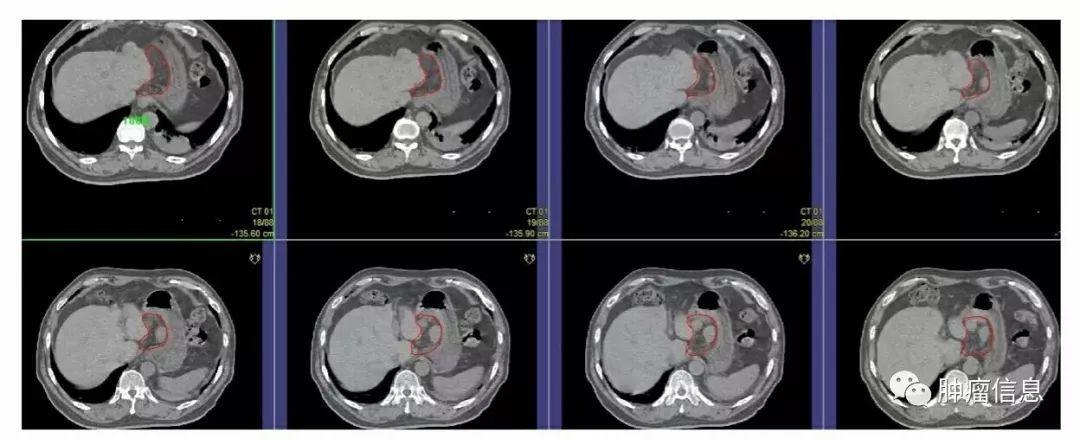

No.16腹主动脉旁淋巴结

上界:腹腔干上缘下界:L3下缘(肠系膜下动脉上缘)